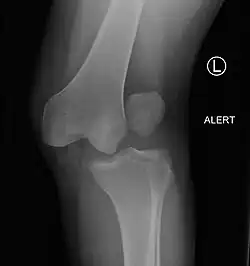

| Plain lateral X-ray of the left knee showing a posterior knee dislocation[1] | |

Plain X-rays, CT scan, ultrasonography, or MRI may help with the diagnosis.[2][11] Findings on X-ray that may be useful among those who have already reduced include a variable joint space, subluxation of the joint, or a Segond fracture.[5]

They may be divided into five types: anterior, posterior, lateral, medial, and rotatory.[4] This classification is based on the movement of the tibia with respect to the femur.[11] Anterior dislocations, followed by posterior, are the most common.[2] They may also be classified on the basis of which ligaments are injured.[2]